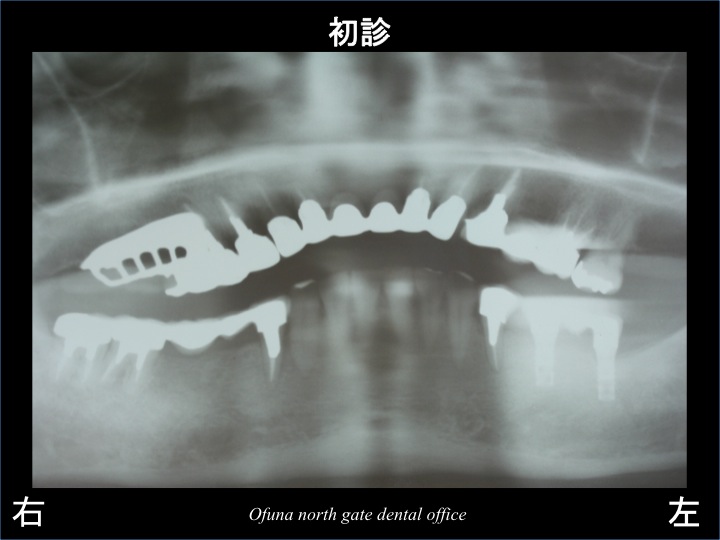

それでは、いつもどおりにレントゲン写真から見ましょう。

以下は、初診時のレントゲン写真です。

15年前の大学病院時代は、現在使用しているようなデジタルレントゲンではなかったため、

フィルムのレントゲンを使用していました。

フィルムのレントゲンは、劣化するので 写りが悪いですが、ご覧になって下さい。

このレントゲンを解説します。

患者様は、噛み合わせに大きな問題がありました。

レントゲンで分かる範囲で説明します。

先にも解説しましたように 患者様の口腔内は

多くの被せ物を装着してありました。

その被せ物自体に問題があったのです。

問題点は多くありますが、最も大きな問題として、

奥歯の被せ物の高さです。

高さが低いのです。

奥歯の高さが低いため、噛み合わせがどんどんとズレてきていたのです。